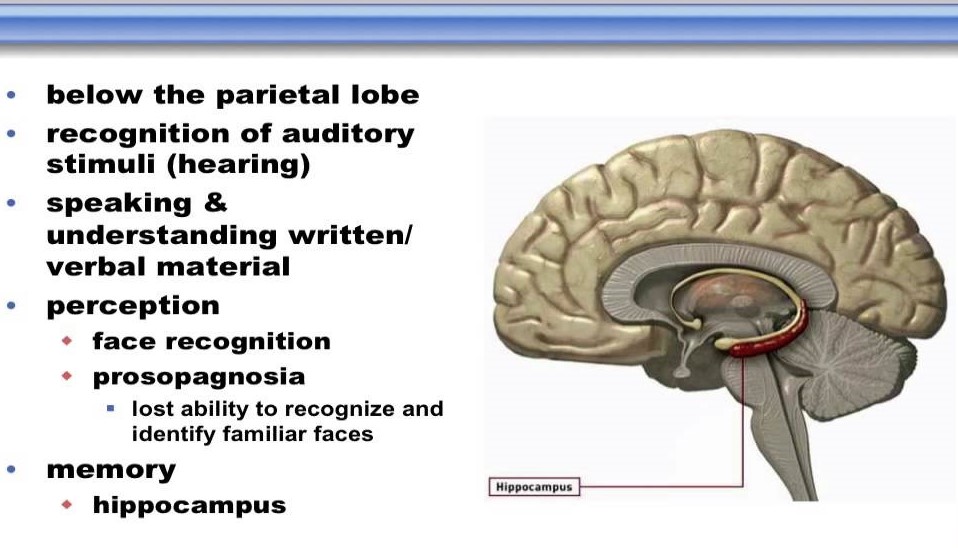

What Is Temporal Lobe

What Is Temporal Lobe

Temporal Lobe Anatomy Location Function Damage Epilepsy

Temporal Lobe Function Anatomy Info

Temporal Lobe Definition Functions Video Lesson Transcript

Temporal Lobe SpinalCord

The Temporal Lobes Are Involved In Memory And Emotion Because

Temporal Lobe SpinalCord

Temporal Lobe The Definitive Guide Biology Dictionary

Temporal Lobe Function Location And Structure

Temporal Lobe

Temporal Lobe What Is It Location Structure Functions Injuries

Temporal Lobe What Is It Location Structure Functions Injuries